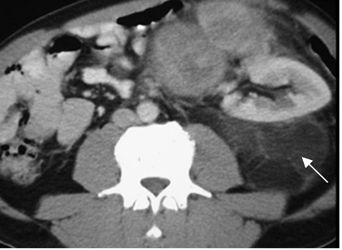

Fig 170. Liposarcoma.

TAC axial. Imagen heterogénea, con densidad de grasa y septos, que ocupa el espacio

para-renal posterior y desplaza el riñón, por liposarcoma retroperitoneal.